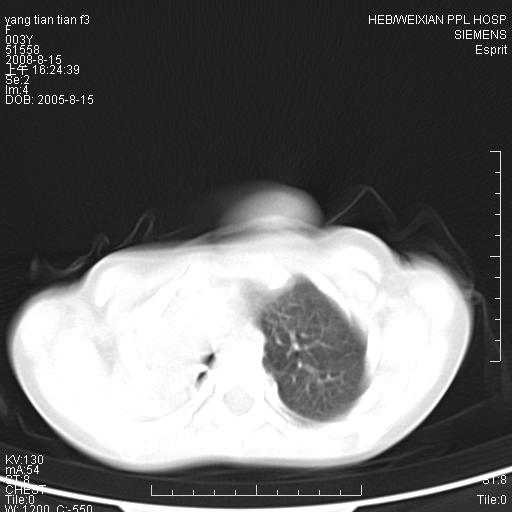

患儿,女,5岁,平素活动后气短,左侧面瘫.右侧胸廓较左侧塌陷.

两侧胸廓不甚对称,左侧稍膨隆,右肺体积明显变小,密度增高,未见正常通气肺组织,纵隔结构明显右移,心脏边缘欠清,外形似增大。纵隔血管间隙不清晰,左肺外形增大,部分肺组织突向右侧胸腔,左肺内未见异常密度影,右侧支气管逐渐变细,其内未见异常密度影。右侧未见叶及段支气管。右侧膈肌升高。

1。右肺体积小(考虑右肺发育不全)

2。左肺代偿性增大

3。心影增大?